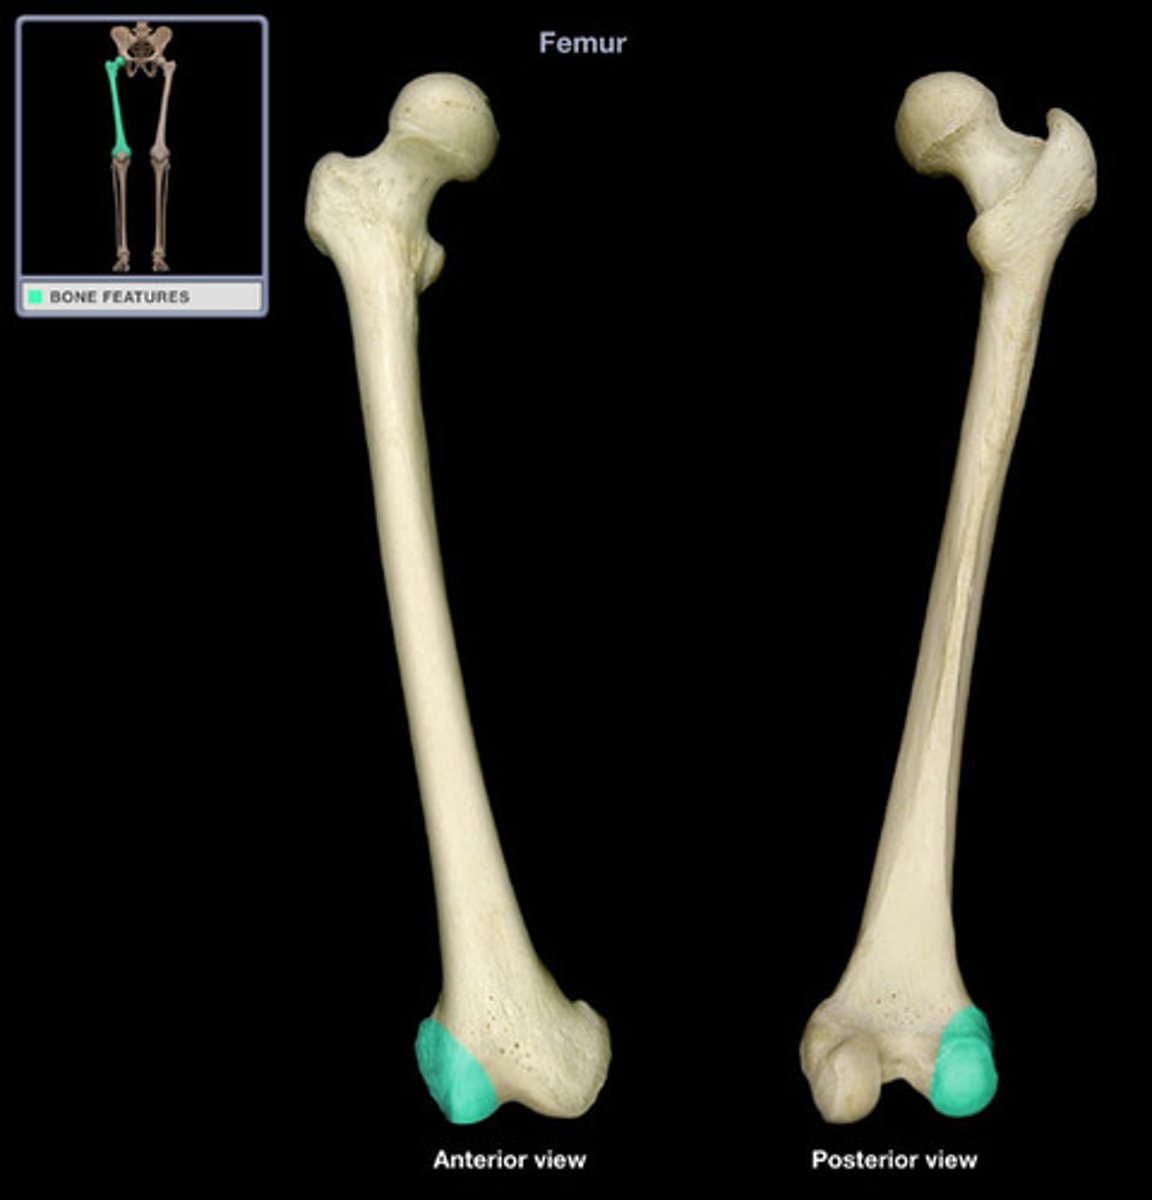

Femur

Head of the Femur

Neck of the Femur

Greater Trochanter

Lesser Trochanter

Medial Condyles of the Femur

Lateral Condyles of the Femur

Medial Epicondyles of the Femur

Lateral Epicondyles of the Femur